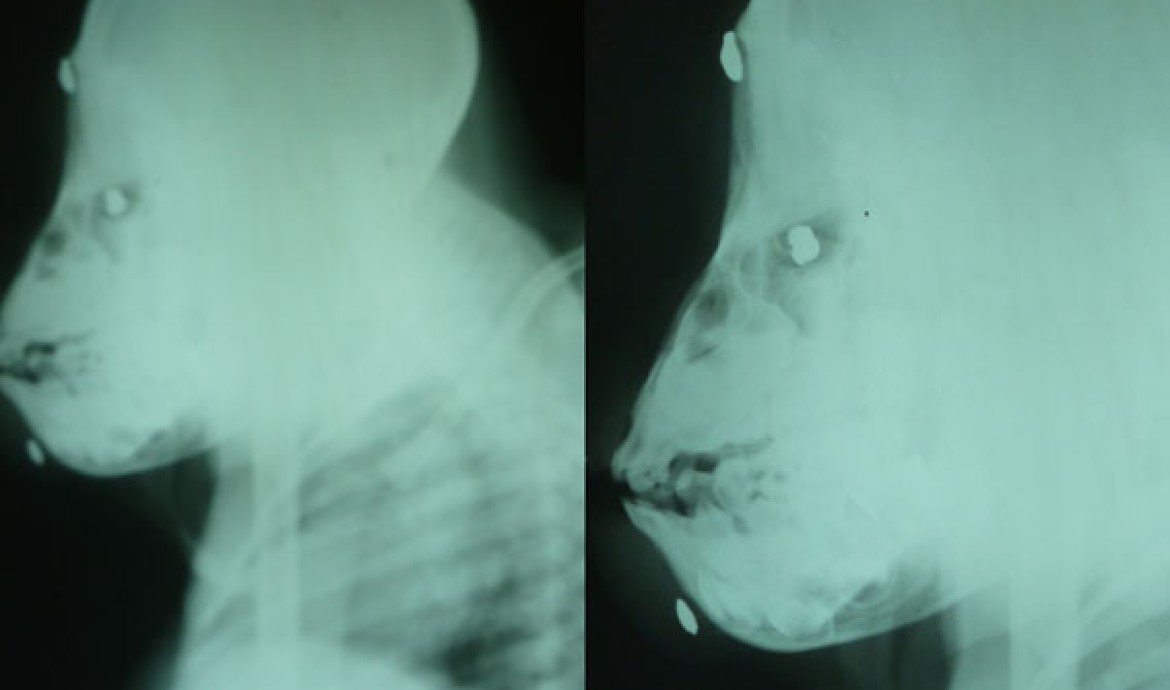

In February 2012, a group of boy scouts found a severely injured orangutan in the Kutai National Park (KNP). They handed the orangutan over to a KNP staff who called a doctor. The doctor was shocked discovering that there were nine gunshot pellets lodged in the orangutan’s body. The doctor and the KNP team tried their best to give treatment to the orangutan, but his condition weakened nevertheless. They finally decided to contact the BOS Foundation in Samboja Lestari.

In Samboja Lestari, the medical team operated on the orangutan and removed all of the pellets in his body. But some pellets that had nested around his right eye had damaged his eyesight, causing him permanent blindness. Outside of these injuries, his condition was quite stable. Our Animal Care Coordinator, Wiwik Astutik, then named the orangutan, Shelton.

Shelton's x-ray results